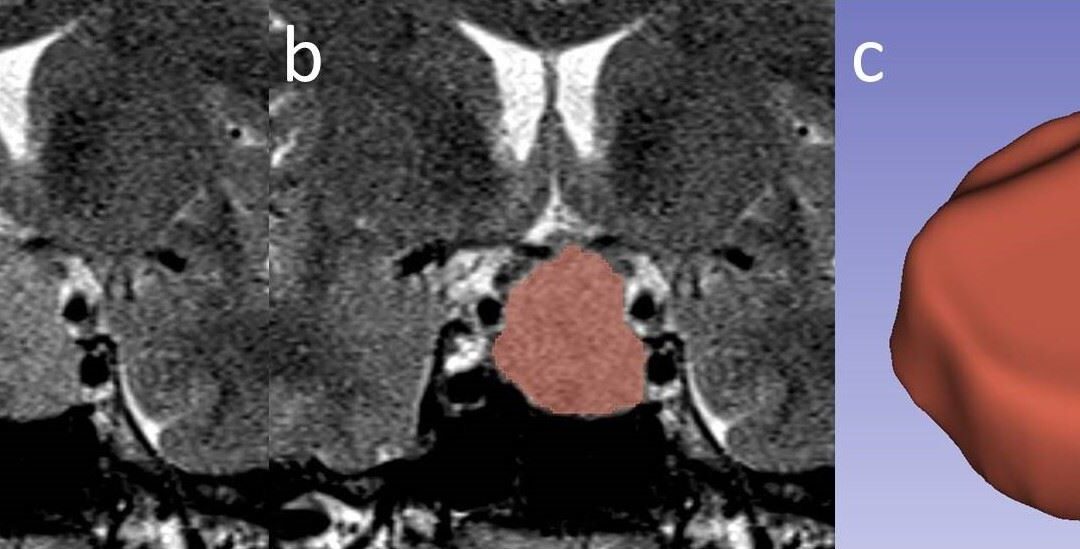

Article: Predicting response to somatostatin analogues in acromegaly: machine learning-based high-dimensional quantitative texture analysis on T2-weighted MRI